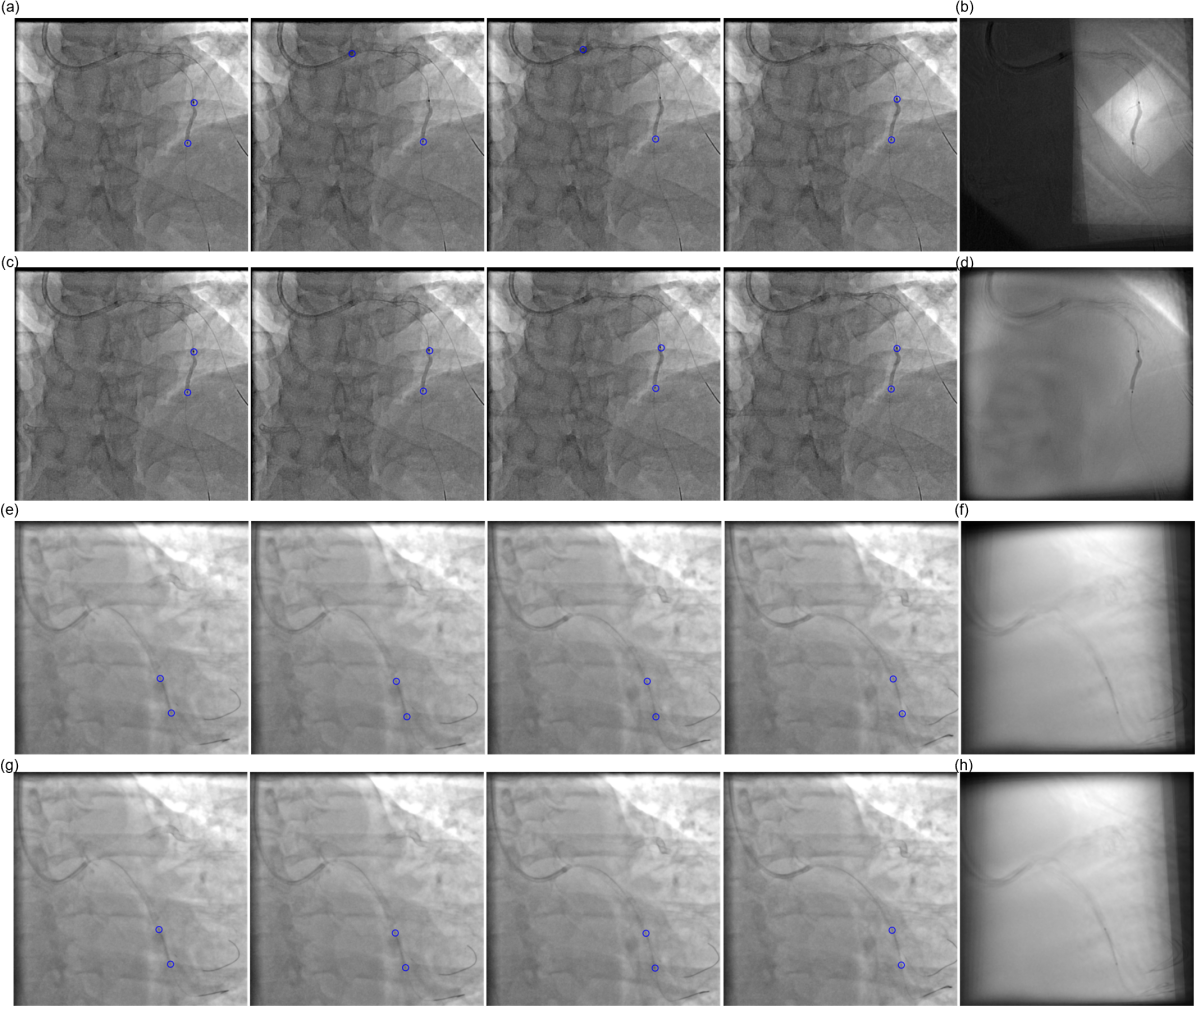

Coronary artery disease (CAD) is one of the primary causes of death in most developed countries [21]. The current state-of-the-art treatment option for blocked coronary arteries is the percutaneous coronary intervention (PCI) (Fig. 1). During this minimally invasive procedure, a catheter with a tiny balloon (the tracked dark object in Fig. 1c) at the tip is put into a blood vessel and guided to the blocked coronary artery. Once the catheter arrives at the right place, the balloon is inflated to push the artery open, restoring room for blood flow. In most cases, a stent, which is a tiny tube of wire mesh (Fig. 1), is also placed in the blocked artery after the procedure to support the artery walls and prevent them from re-narrowing. Intraoperative X-ray fluoroscopy is commonly used to check the location of stent/balloon before expansion. However, stent visibility is often limited (Fig. 1a and c) under X-ray because the minimal level radiation dose out of safety concerns. Furthermore, stents keep moving rapidly with heartbeat and breathing in the complicated environment of patients’ anatomy.

Compared to other physical approaches, such as invasive imaging or increasing radiation dose, a more cost-effective solution is to enhance the stent appearance through image processing (a.k.a., digital stent enhancement), as shown in Fig. 1b and d. A common method is to track the stent motion, separate the stent layer from the background layer, and average the stent layers from multiple frames after motion compensation. Stent tracking is achieved by tracking two radiopaque balloon markers that locate at two ends of the stent (Fig. 1).

Refer to caption

Figure 1: Examples of stent tracking with the proposed method (a,c) and stent enhancement based on the tracking results (b,d). a and c show four frames from a video.